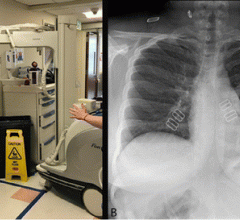

April 17, 2020 — To date, the radiology literature on coronavirus disease (COVID-19) pneumonia has consisted of limited ...

April 14, 2020 — Chest X-rays are often used to detect infections in the lungs, but the world’s largest study of its ...

April 10, 2020 — Radiology departments must prepare for patient surges through streamlined approaches to imaging that ...